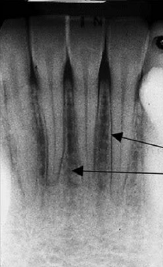

70. What is showing by arrow?

Alveolar bone Normally the level of the alveolar bone is 1.5-2mm apical to the CEJ of the adjacent teeth. In the anterior region the crest is sharp and pointed between the incisors. Posteriorly it is flat, aligned parallel with and slightly below a line connecting the CEls of the adjacent teeth.

71. What is showing by arrow?

"Lamina Dura" : a thin radiopaque layer of dense bone bounding the tooth socket. It is continuous with the shadow of the cortical bone at the alveolar crest. The presence of an intact lamina dura around the apex of a tooth strongly suggests a vital pulp.

72. What is showing by arrow?

> Periodontal ligament (PDL) • Radiographically seen as a radiolucent line on inside of lamina dura PDL is thinner in the middle of the root and slightly wider near the alveolar crest and root apex average width: 0.5 mm). Position in relation to tooth can determine if lesion is attached to tooth structure (inside PDL) or not (outside PDL). Widening of the periodontal ligament space: Increased width of periodontal ligament space due to inflammation. Etiology: pulp necrosis, root fracture, trauma from occlusion, malignancies, scleroderma (generalized PDL)